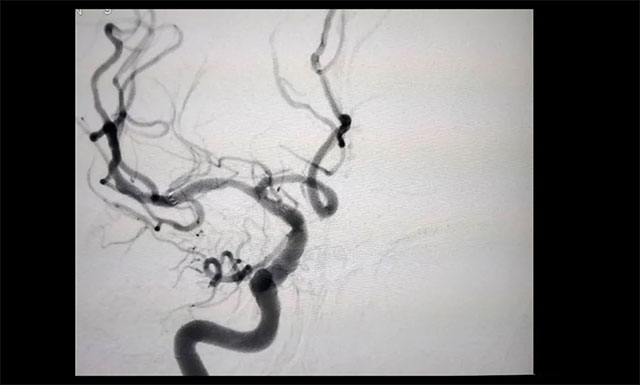

在临床上,DSA被称为诊断脑血管病变的“金标准”。其全称是数字减影血管造影 ( Digital Subtraction Angiography,DSA ) ,是将常规血管造影与计算机技术相结合的一种高端诊疗技术。

李振并主任介绍,DSA不但能清楚地显示颈内动脉、椎基底动脉、颅内大血管及大脑半球的血管图像,还可测定动脉的血流量,不但能提供病变的确切部位,而且让医生对病变的范围及严重程度,也能清晰了解,为治疗提供可靠的客观依据。

▲ 患者右侧大脑中动脉M1段重度狭窄

经行 DSA 检查,胡老伯右侧椎动脉纤细,右侧大脑中动脉 M1 段重度狭窄(约80%-90%),只剩下不到20%的空间,血流明显受阻。李振并主任表示,大脑中动脉是颈内动脉的延续,它供应大脑外侧面3/4的血液,所以大脑中动脉狭窄后会导致部分区域血流不足而引起相关症状。严重时会出现偏身运动障碍、偏身感觉障碍,甚至昏迷。一般情况下,当大脑中动脉狭窄程度超过70%,需要及时进行支架植入治疗,同时要注意其他危险因素的预防。